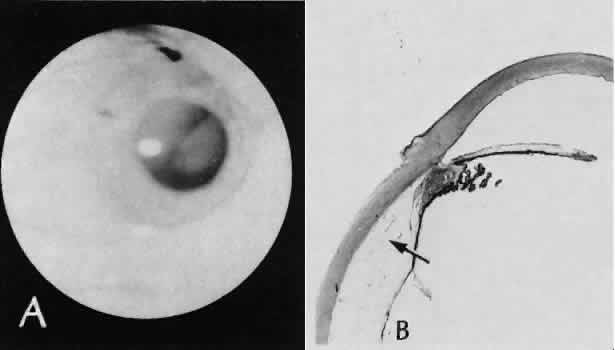

A flat anterior chamber is characterized by anterior displacement of the iris to near or in actual contact with the posterior surface of the cornea. The most common cause is leakage of aqueous along one of the suture tracks. Prolonged decompression of the anterior chamber increases the risk of synechiae formation and intractable secondary closed-angle glaucoma. Corneal endothelial damage may result in bullous keratopathy. Choroidal edema (choroidal hydrops or detachment) (Fig. 31) may be associated with a flat anterior chamber and may potentiate the condition. The choroidal edema will slow or stop aqueous production by the ciliary body, further delaying reformation of the anterior chamber. The histologic characteristics of choroidal edema consist of spreading of the choroidal tissue in a fanlike configuration and eosinophilic fluid filling the intervening spaces. The edema fluid may be lost in processing, leaving multiple apparently empty spaces.

Fig. 31. A case of choroidal detachment. A. By fundus reflex, a large dome-shaped mass can be seen originating from the choroid. The differential diagnosis would include uveal malignant melanoma. In this case, the clinical findings were due to choroidal detachment from the sclera because of fluid accumulating in the suprachoroidal space following cataract surgery. B. The histologic section from another case of choroidal detachment illustrates the location (arrow) and extent of the detachment. In this case the detachment extends to the region of the ciliary body limited anteriorly by the attachment of the choroid to the scleral spur. The displacement of the ciliary body will result in apparent shallowing of the anterior chamber. (Hematoxylin-eosin stain; × 6.)